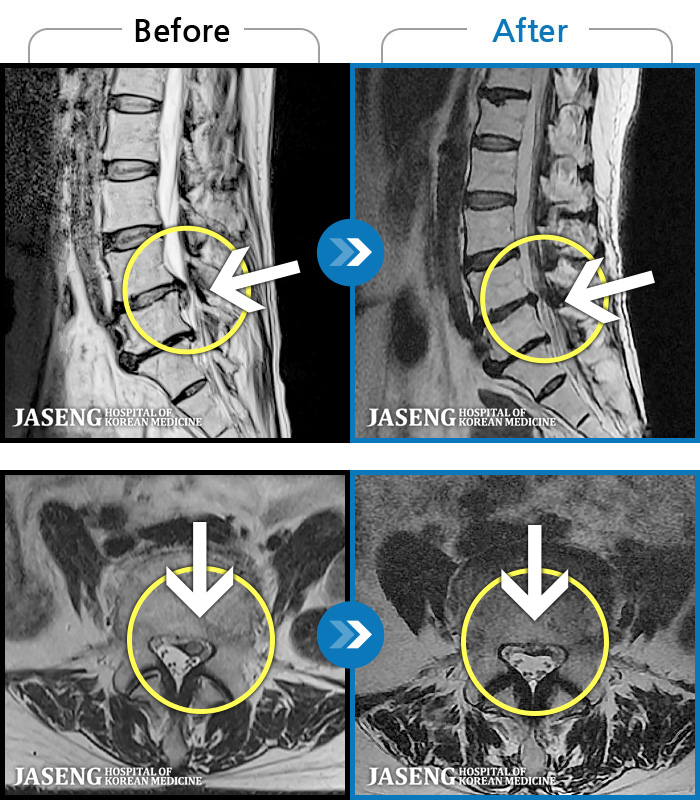

MRI ġ

1,237 MRI ũ ʸ Ȯϼ.